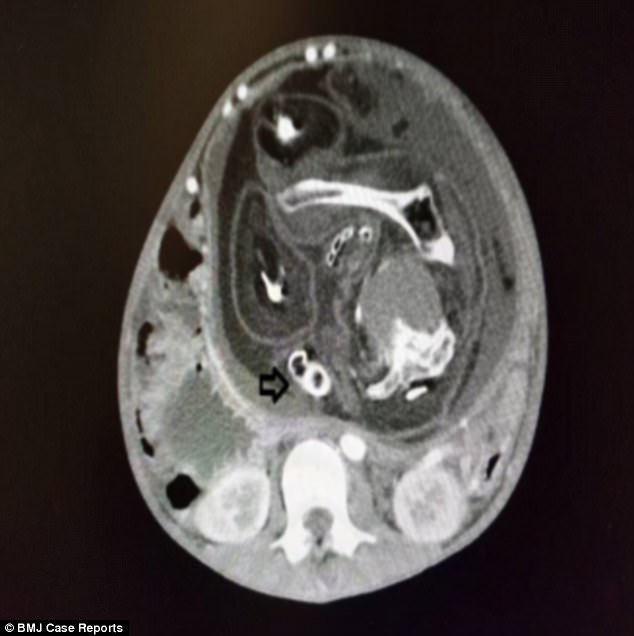

Nhưng gần đây, khi cậu bé cảm thấy bụng phình to, cứng phần bụng trên và rất khó chịu, gia đình mới đưa tới bệnh Sultan Abdul Halim ở Sungai Petani, Kedah, Malaysia để thăm khám. Tại đây, các bác sĩ tiến hành chụp CT và cho thấy trong bụng cậu bé có một vật thể lạ dài 23,8cm và nghi ngờ là khối u ung thư.

Hình ảnh chụp CT trong bụng cậu bé Malaysia.